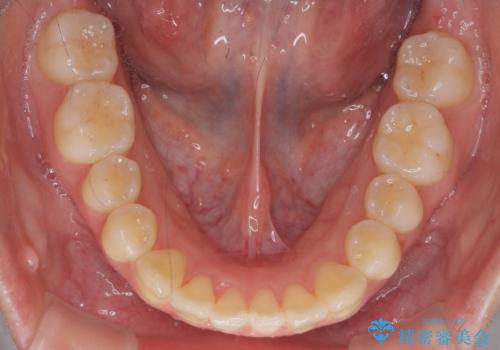

年齢が10代なこともあり、歯の動きは非常によく、リファインメントなしできれいに並びました。

下の前歯を少し削合して並べています。